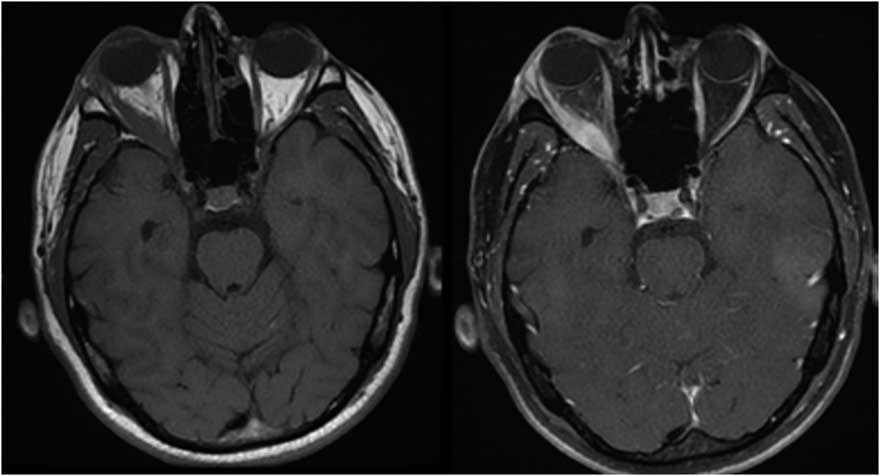

Case 3: A 74-year-old male was admitted with a 1.5-year history of blurred vision and progressive bulging of both eyes. The symptoms started after nasolacrimal duct intubation surgery to treat lacrimal drainage obstruction. He had a past medical history of vision loss in his left eye due to trauma 10 years previous, as well as erosion and perforation of the nasal septum 2 years before. Neurological examination showed bilateral proptosis that was more prominent on his right eye, and his extraocular movements were limited bilaterally in all directions (Figure 3a). MRI of the orbit identified bilateral hyperintensities, enlargement, and contrast enhancement in extraocular muscles. Brain MRI findings included linear dural thickening and enhancement on the anterior frontal and temporal lobes, inflammation and enhancement on the maxillary, frontal, and sphenoid sinuses, and a nasal septum defect (Figure 3b). Investigations revealed a mild increase in CRP and sedimentation rate, slightly low T3 and T4 levels, and normal thyroid-stimulating hormone, CBC, antithyroid antibodies, viral serology, IgG4 levels, ANA, and anti-AChR antibodies. The anti-proteinase ANCA (anti-PR3 ANCA) level was 72.3 U/ml (>20 U/ml), and p-ANCA was found to be positive. Therefore, a diagnosis of orbital inflammation due to GPA was established. Chest CT revealed calcific lung nodules and bilateral apical pleuroparenchymal fibrotic density changes. Histopathological investigation of nasal biopsy revealed chronic inflammation. He was treated with high-dose IV methylprednisolone (1 mg/day for 5 days) followed by 60 mg/day oral prednisolone. He responded with a prompt reduction of proptosis and lid edema and a slight improvement in ocular movement over the 6-month period. Treatment continued with prednisolone tapering and azathioprine.

Figure 3b Axial and coronal MRI showing bilateral hyperintensities, enlargement, and contrast enhancement in extraocular muscles, linear dural thickening, and enhancement on the anterior frontal and temporal lobes, enhancement on the maxillary, frontal, and sphenoid sinuses and nasal septum defect. Right bulbus oculi was normal, whereas left bulbus oculi revealed retinal detachment.